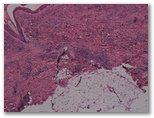

R3-1514-Mujer de 35 años, sin antecedentes patologicos relevantes que consulta por adenopatías hiliares y las lesiones cutáneas que observas en la imagen y en la biopsia.

a)descripción, dx, formas clínico-patologicas

Diagnostico